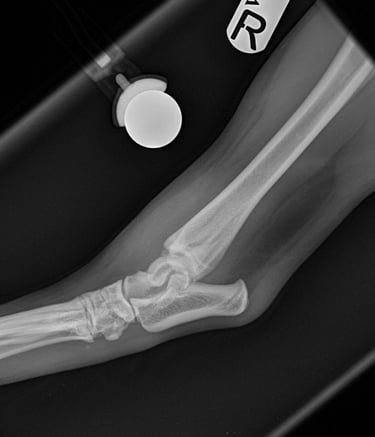

Orthogonal xrays reveal a lateral malleolus fracture (Fig.1 and 2), stress views and palpation revealed stable joint with no affection of collateral ligaments but due to the fracture there is some degree of rotational instability. Surgical stabilization is strongly advised as Buddy is a 40 kg patient.

Fig. 2

Fig. 1